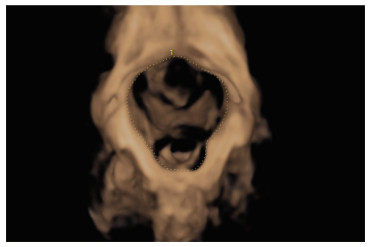

1.2.2.2 操作方法经阴道超声观察盆底结构,膀胱适度充盈,取截石位,充分暴露会阴部,将耦合剂涂抹于探头表面,用探头套包裹探头,将探头轻置于会阴部;显示盆底矢状切面图像,见图 1。观察耻骨联合(pubic syphilis,PS)、尿道(urethra,UR)、膀胱(bladder,BL)和膀胱颈(bladder neck,BLN)。在二维测量2组孕妇膀胱颈位置(D)、尿道倾斜角(β)、膀胱尿道后角(poster urethrovesical angle,PUVA),分别测量静息及张力状态下膀胱颈位置(D1、D2)、尿道倾斜角(β1、β2)、膀胱尿道后角(PUVA1、PUVA2),并计算膀胱颈移动度(bladder neck descent,BND)、尿道旋转角度(urethra rotation angle,URA)。在静息及张力状态下启动三维成像,获取肛提肌裂孔面积(levator hiatus area,LHA),见图 2,测量2组孕妇不同状态下LHA(LHA1和LHA2)。

| 图 2 首次妊娠组张力状态下肛提肌裂孔面积 Fig.2 Levator hiatus area on valsalva in the first pregnancy group |